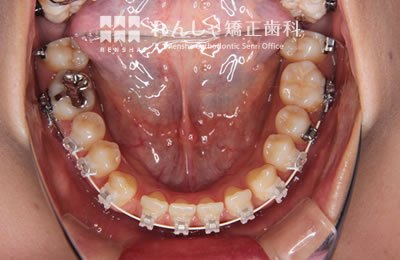

中高生

永久歯列はほぼ完成してしますが、歯列を側方だけでなく後方へも拡大し、埋まっていた右上奥歯を引っ張り出しています。

治療中

→

| 主訴 | 埋まったままでてこない歯がある |

|---|---|

| 診断名 | Angle Class II 小臼歯の埋伏と叢生を伴う上顎前突 |

| 初診時年齢 | 13歳5か月 |

| 装置名 | マルチブラケット装置 |

| 抜歯非抜歯 | 非抜歯 |

| 治療期間 | 2年3か月 |

| 費用の目安 | 約82万円+消費税(検査料金、都度の処置費用等も合わせた総額) |

| リスク副作用 | 歯の移動に伴う軽微な歯根吸収、歯槽骨吸収、歯肉退縮(本症例では軽度の歯根吸収を認めた)、矯正器具装着中のカリエスリスク増大(本症例ではカリエス発生無し) |